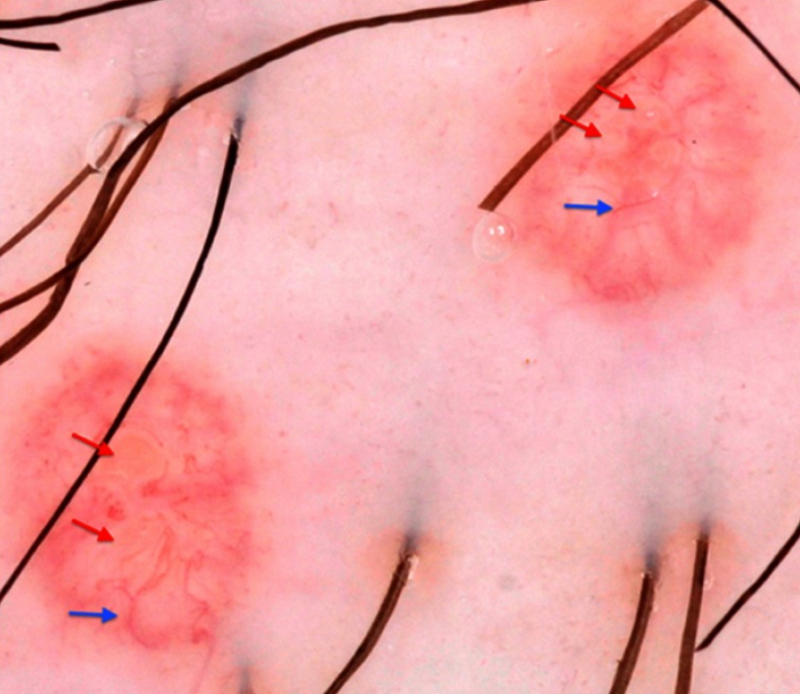

Dermatoscopic findings of Molluscum contagiosum. Red arrows indicate white-to-yellow polylobular structures; blue arrows: crown vessels. (Polarised-light dermoscopy, original magnification 10x)

Clinical, Cosmetic and Investigational Dermatology 2019:12 373-381. Originally published by and used with permission from Dove Medical Press Ltd.